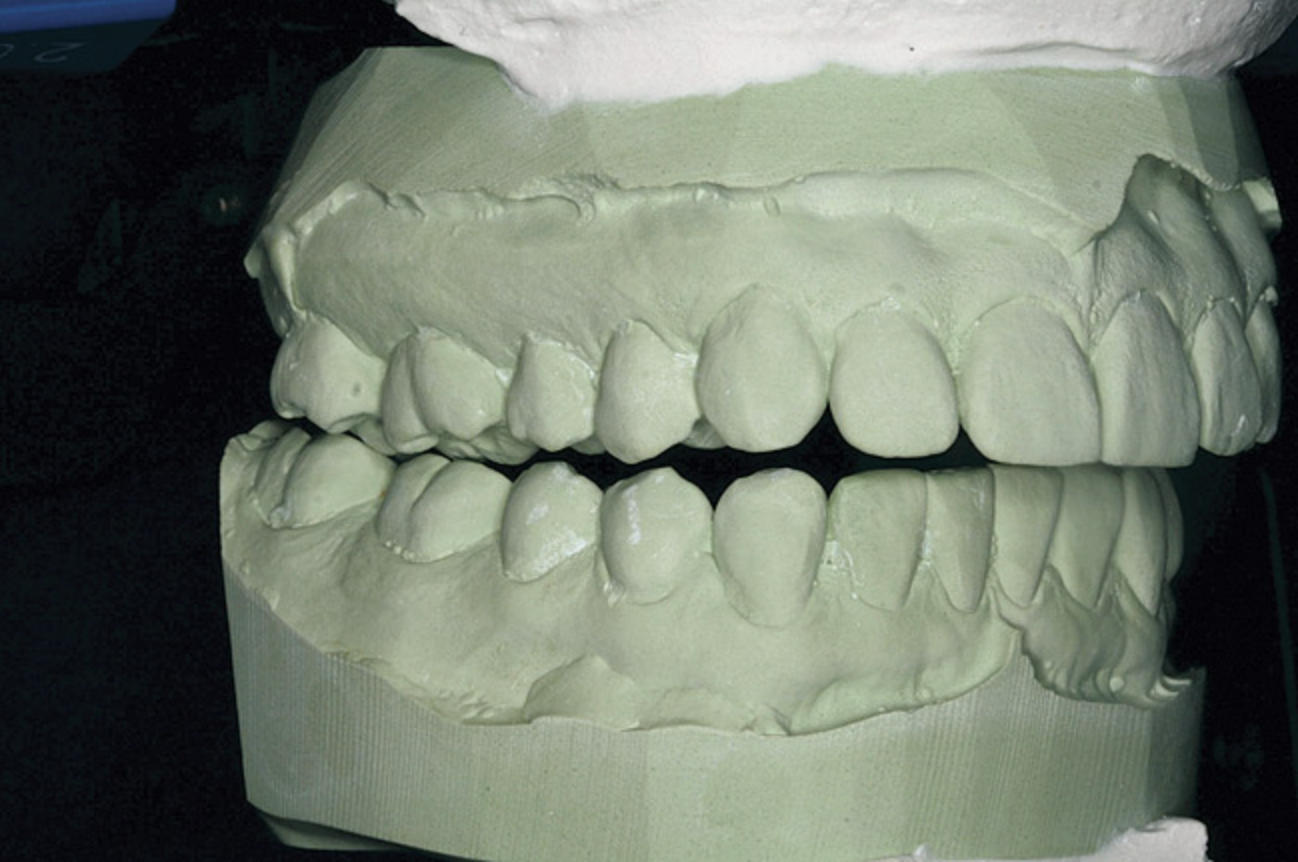

Figure 1  Dental midlines should be as close to coincident as possible. Gingival height of maxillary lateral incisors should be even with a line between the gingival height of the central incisor and canine to 1.5 mm below that line.

Figure 1

The dental midline can be improved within limits by restorative procedures. However, if orthodontic alignment is to be performed, the orthodontist plans treatment to ensure the position and vertical axis of the midline is harmonious with the facial esthetics (Figure 1).